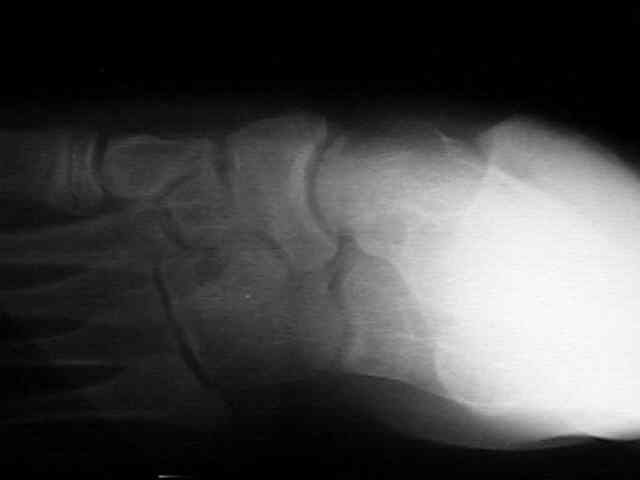

Radiographs

• radiographs may not be helpful if the accessory ossification is not ossified;

• the standard oblique of the foot (medial internal oblique view) will not show the accessory ossicle in profile;

• the lateral (external) oblique view is the radiograph of choice;

• although accessory navicular appears distinct from the navicular on x-rays, it is actually attached by fibrous tissue or cartilage;

Accessory Navicular 2 Accessory Navicular 3 Accessory Navicular 4